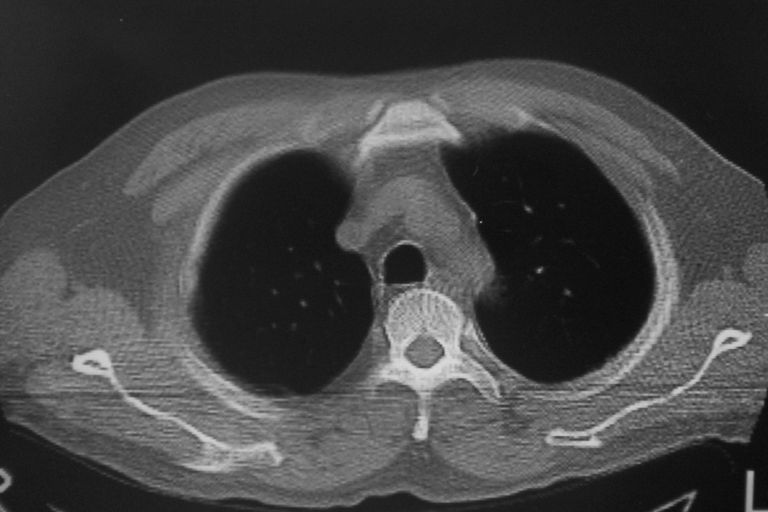

标题: CT10574:男 50岁胸部CT请会诊!

患者 男 50岁 无痛性咯血3天,无其他不适.

左下肺结节状软组织密度影,边缘有毛刺,考虑周围型肺癌。

1 左肺下叶基底段见两结节软组织密度灶, 肺窗边缘见有毛刺征像, 不能排除占位. 2 建议结合临床治疗一周后ct随访在看其结果.

临近胸膜增厚,病变周围肺不清,稍有分叶。结节密度略高,肺、纵隔窗差异不大,肺癌待排。前方还有一个

1 左肺下叶后基底段见结节软组织密度灶,周围见毛刺,建议抗炎后复查,警惕周围型肺癌。

2 心包积液。

左下肺结节状软组织密度影,一个边缘有卫星病灶,邻近胸膜增厚.另一个有毛刺.心影周围水样密度影环绕.考虑:

1.肺癌可能.肺tb待排.

2.左侧胸膜增厚.心包积液.